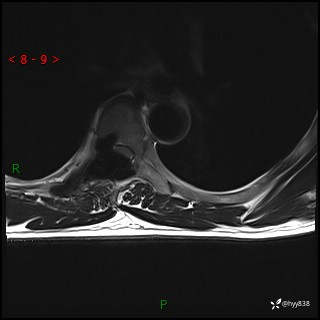

axi T2WI